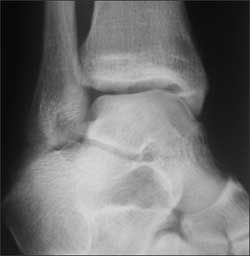

(Answer on next page.)Right ankle pain after a basketball injury: The frontal view of the ankle reveals soft tissue swelling that is predominantly lateral (A, yellow arrow). A small ossific fragment is evident distal to the lateral malleolus (A, white arrow); close inspection shows this to be well-corticated. The remainder of the osseous structures are intact. The lateral view reveals a joint effusion in the talotibial joint (B, arrow); no fractures are visible. In the oblique view (C), the osseous structures appear intact.

The well-corticated ossific fragment is consistent with an old injury, but it is in the region that is now extremely tender. The joint effusion indicates that the current injury is severe. However, this is a nonspecific finding; joint effusions are seen with fractures and ligament and tendon injuries.